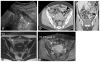

The appendix may demonstrate a perplexing range of normal and abnormal appearances on imaging exams. Familiarity with the anatomy and anatomical variants of the appendix is helpful in identifying the appendix on ultrasound, computed tomography, and magnetic resonance imaging. Knowledge of the variety of pathologies afflicting the appendix and of the spectrum of imaging findings may be particularly useful to the emergency radiologist for accurate diagnosis and appropriate guidance regarding clinical and surgical management. In this pictorial essay, we review appendiceal embryology, anatomical variants such as Amyand hernias, and pathologies from appendicitis to carcinoid, mucinous, and nonmucinous epithelial neoplasms.